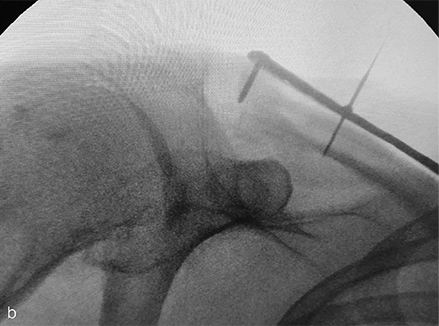

Figure 1a–c Distal clavicular fixation during prototype evaluation of the novel VA Clavicle System. Lateral is to the left in all figures. Conformation of the plate to the superior topography of the distal clavicle is designed to facilitate positioning of the distal margin of the plate parallel to the acromioclavicular joint (a) and respects the almost universal 12o downward tilt of the distal clavicle in the lateral fifth of the bone (b), while also allowing the plate to follow the beginning of the twist region at the junction of the second and third fifths of the bone (c).